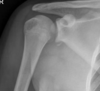

Anterior shoulder dislocation

Posterior shoulder dislocation